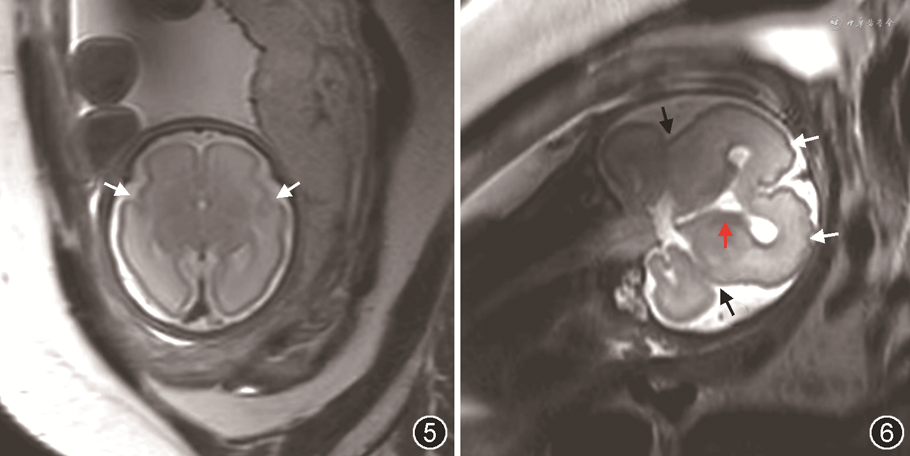

2.神经系统MRI检查:12例中,10例胎儿行神经系统MRI检查,2例拒绝检查而直接选择引产。MRI与超声检查对于胎儿MCD的各种异常征象基本一致(表1和2)。大脑外侧裂异常胎儿MRI图像见图5和6。病例1的MRI显示大脑半球表面多微小脑回,但NSG漏诊。病例3和5的MRI显示胎儿脑实质内异常灰质分层,而NSG漏诊;病例3和7的NSG显示胎儿胼胝体发育不良,但MRI漏诊。

本研究结果显示,胎儿NSG与MRI不仅显示的大脑外侧裂形态一致,而且同样显示了其他一部分MCD可能的征象,如侧脑室形态异常、神经节隆起增厚或腔化等。但是NSG检查无法完全避开颅骨对于脑组织表面的遮挡,所以漏诊了额叶表面多微小脑回。由于超声无法显示灰质细胞,所以会漏诊白质内异常的灰质异位及分层。但是部分NSG发现的胎儿胼胝体发育不良也被MRI漏诊。2021年ISUOG指南指出经阴道NSG对于评价胼胝体发育不良较MRI准确[8]。提示MRI及NSG检查在MCD的产前诊断中起到互相印证、互相补充的作用,均不可或缺。